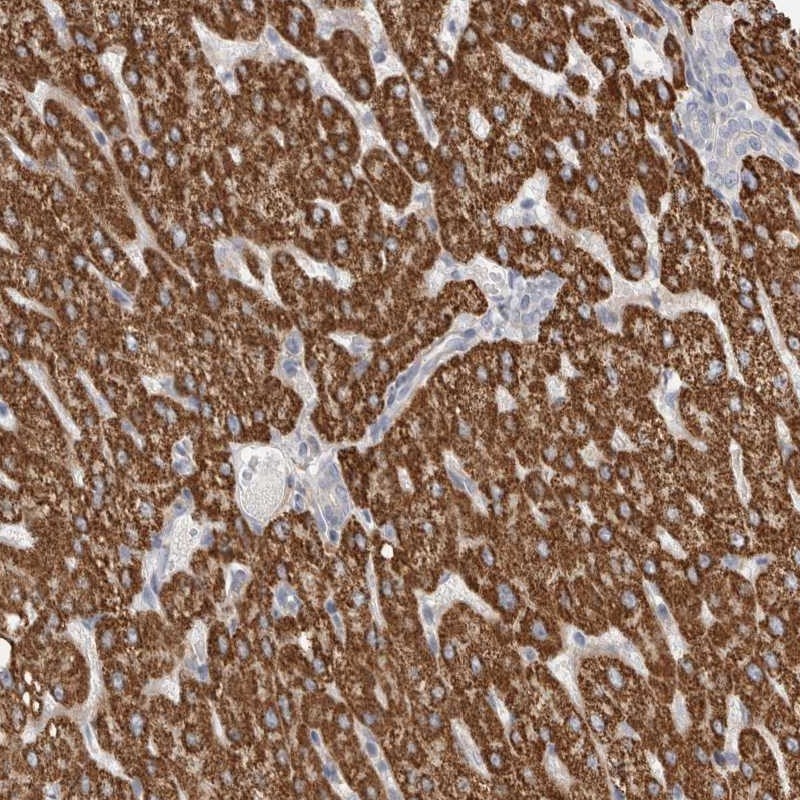

Immunohistochemical staining of human liver shows strong granular cytoplasmic positivity in hepatocytes.